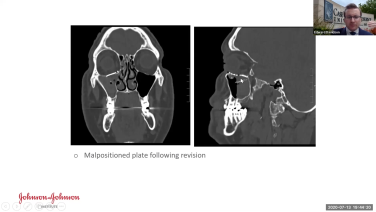

Concepts in Orbital Reconstruction: Established Post-traumatic Globe Malposition with Edward Davidson, MD

Concepts in Orbital Reconstruction: Techniques with Edward Davidson, MD

Concepts in Orbital Reconstruction: Approaches with Edward Davidson, MD

Concepts in Orbital Reconstruction: Timing with Edward Davidson, MD

Concepts in Orbital Reconstruction: Surgical Indications with Edward Davidson, MD

Concepts in Orbital Reconstruction: Anatomy with Edward Davidson, MD